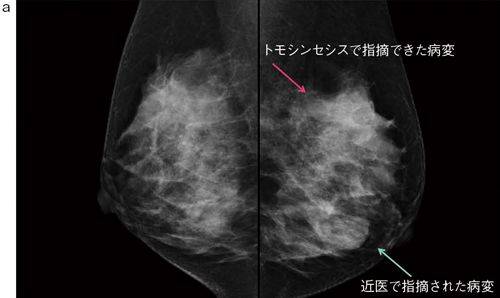

■症例1:40歳代後半,女性。両側乳房腫瘤を自覚,近医で良性と診断。超音波フォロー中に新規病変を指摘されて当院へ紹介。

a:左右MLO画像

b:左MLO拡大画像(左),トモシンセシス拡大画像(右)

c:造影MRI矢状断像,Bモード画像,病理像